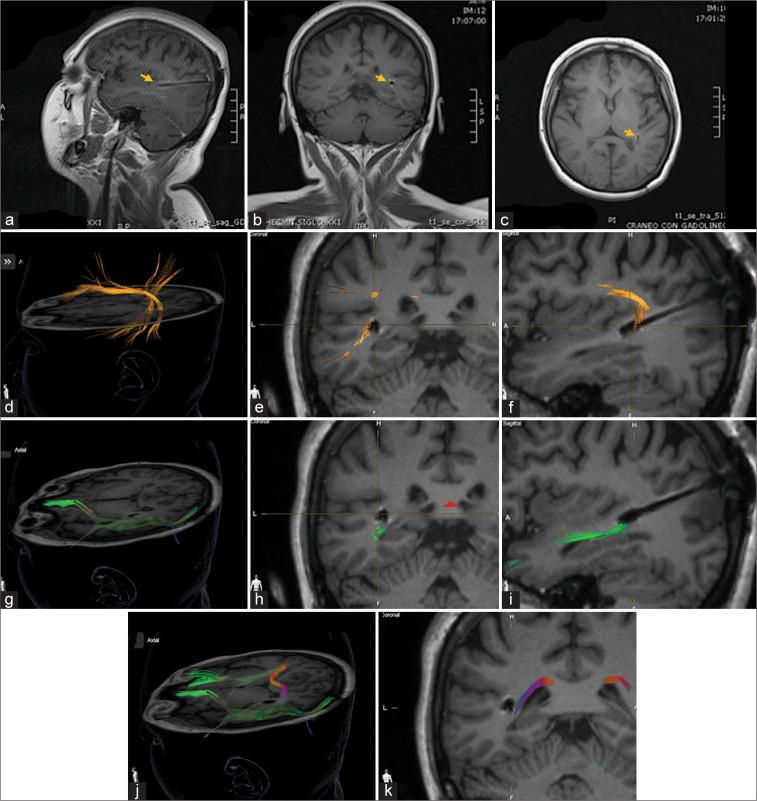

This report aims to describe the neuromodulation effect on seizure control in a patient with a left hippocampal migrated electrode to the Posterior Sylvian Junction (PSJ) during a follow-up of 17 years.

We report a case of a female patient with drug-resistant epilepsy who initiated at seven years old and underwent a stereotactic frame-based insertion of a left hippocampal electrode for deep brain stimulation (DBS). Posterior migration of the electrode was identified at PSJ by postoperative magnetic resonance imaging one month after surgery. A consistent seizure reduction (Engel IC) was obtained with 2v-120 uS-145 Hz, contacts 0-3 negative, casing positive DBS parameters and maintained to this day. Patient data were collected from electronic medical records preceded by obtaining an informed consent for research and publication purposes. Stimulation parameter adjustments were confirmed with the digital records of the local device provider (Medtronic).

PSJ is a connectivity confluence point of white matter pathways in the posterior quadrant of the hemispheres. White mater DBS could be considered for research as a potential complementary target for neuromodulation of refractory epilepsy.

本报告旨在描述在17年的随访期间,左侧海马电极迁移至后颞叶沟回(PSJ)的患者中神经调节对癫痫控制的影响。

我们报告一例耐药性癫痫女性患者,其癫痫始于7岁,接受了基于立体定向框架的左侧海马电极植入术以进行深部脑刺激(DBS)。术后1个月的磁共振成像显示电极在PSJ处发生向后迁移。采用2伏-120微秒-145赫兹、触点0-3负极、外壳正极的DBS参数可使癫痫发作持续减少(Engel IC级),且这种效果一直维持至今。患者数据从电子病历中收集,收集前已获得用于研究和发表目的的知情同意书。刺激参数调整通过当地设备供应商(美敦力公司)的数字记录得以确认。

PSJ是半球后象限白质通路的连接汇合点。白质DBS可作为难治性癫痫神经调节的潜在补充靶点进行研究。